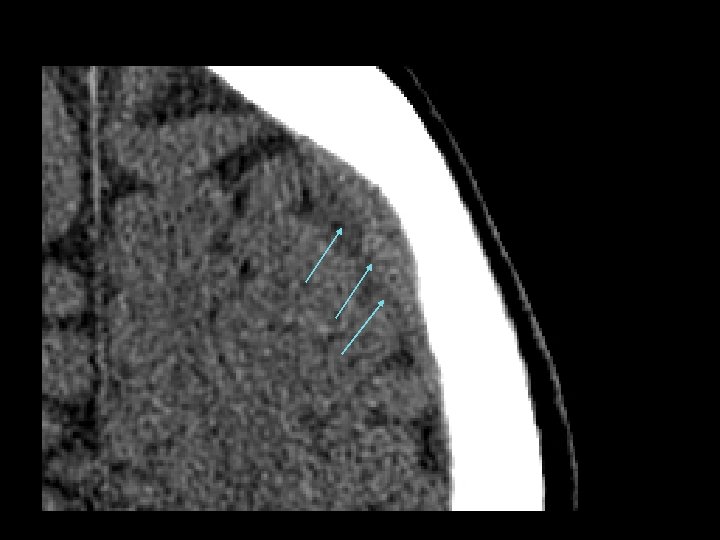

Diffuse Axonal Injury (DAI) • Shearing and rotational forces disrupt the axonal network • Mechanism: rapid acceleration/deceleration injury • Imaging – Not well visualized by CT – MRI can better define the extent of injury • No specific therapy • Likely results in the persistent neurologic deficits in patients with normal CT scans but substantial injury